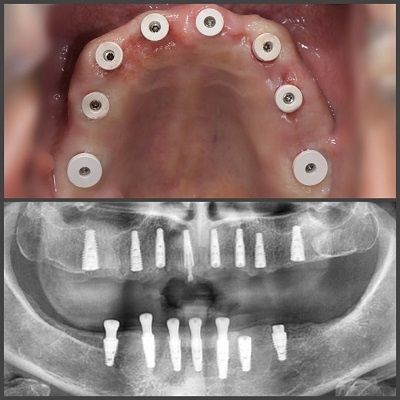

- درمان بیماریهای لثه: در صورت بروز بیماریهای لثه، دکتر لثه باید بتواند روشهای درمانی مؤثر را ارائه دهد. این شامل تمیزکردن دندان پروفسیونال توسط دکتر، جراحیهای لثه، درمان دارویی و سایر روشهای تسکینی است.